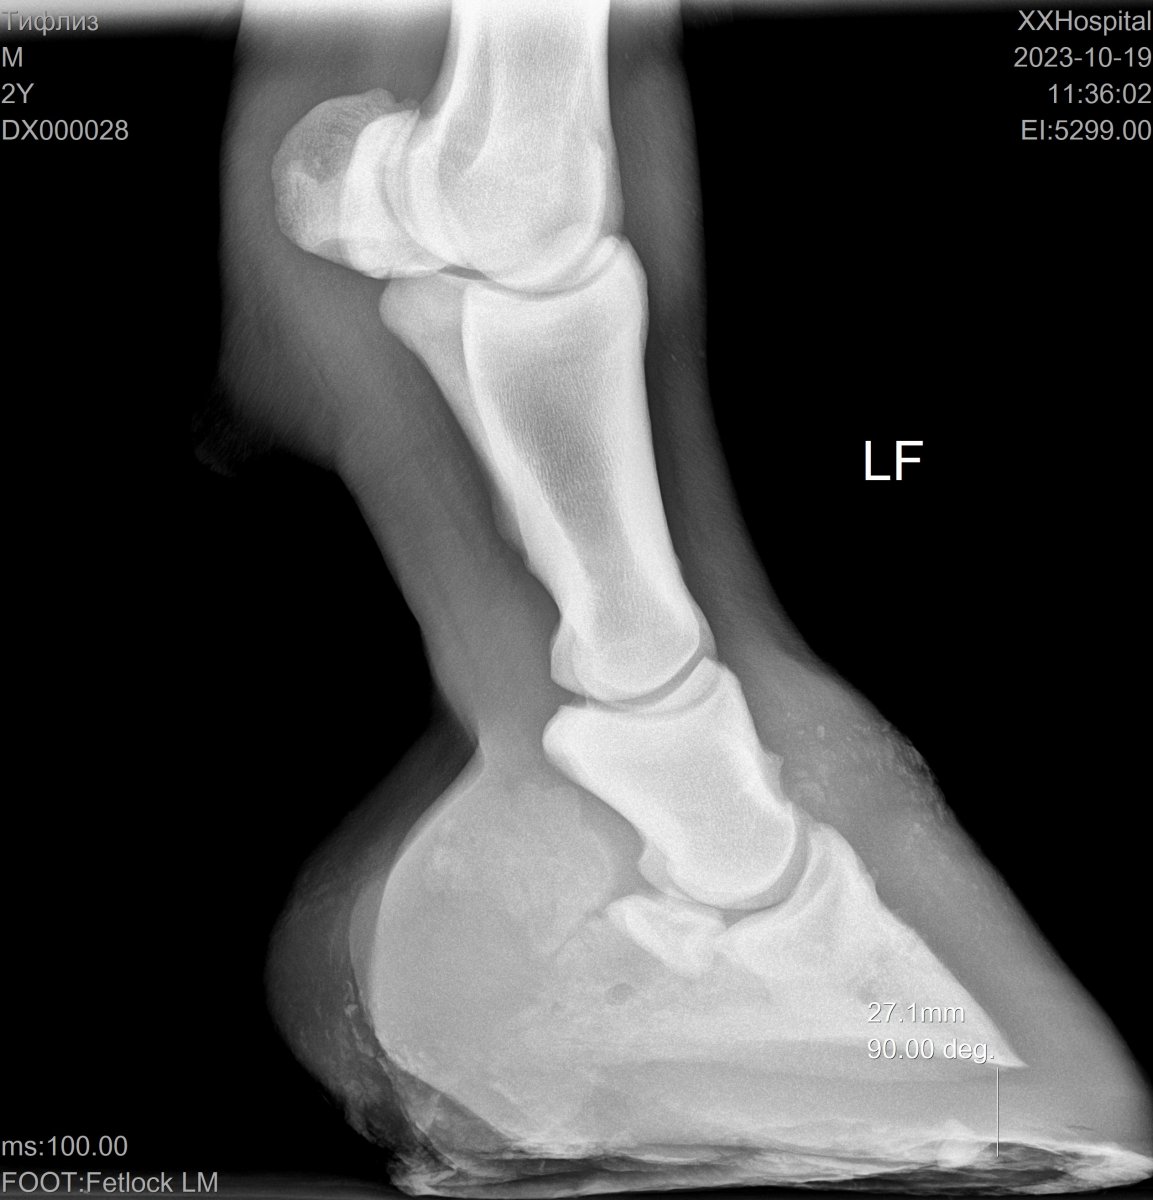

Да так по брови, что подошвы 27 мм.

Вложения

• DX000028_2.jpg

DX000028_2.jpg

136.1 KB · Просмотры: 95